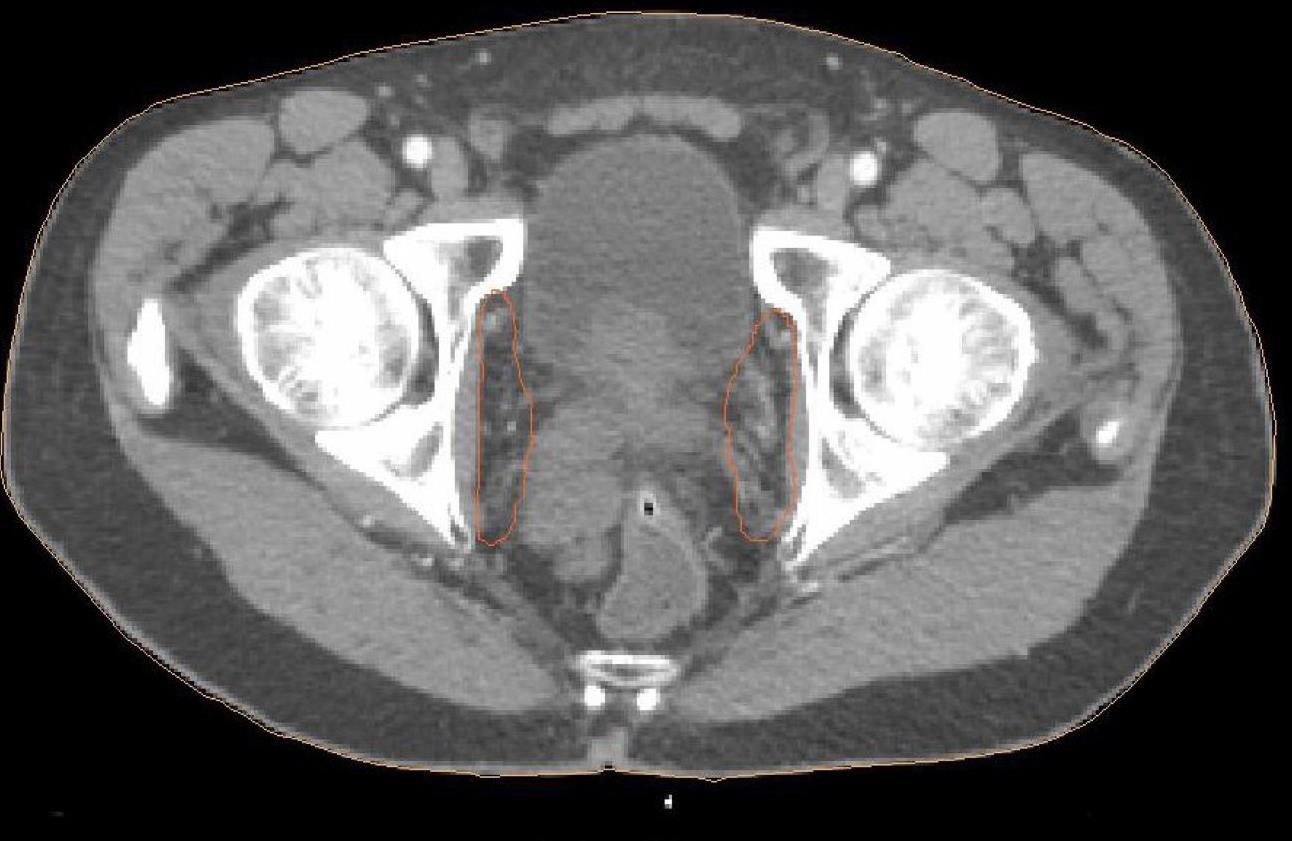

Na poniższym przekroju poprzecznym strzałką zaznaczono węzły chłonne: